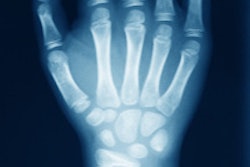

Specifically, the group identified 31 types of clinical indications for wrist imaging, of which 16 received the highest appropriateness rating. Ultrasound is not indicated for hamate fractures, triangular fibrocartilage complexes, capitate fractures, Kienböck's disease, or hamatolunate impingements, they noted.